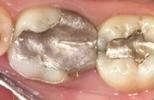

All Porcelain Posterior Crown and Filling

Concerned that their old-fashioned crown and filling were drawing unwanted attention to their smile, this patient requested new, all-porcelain cosmetic work.

CEREC Same-Day Crowns